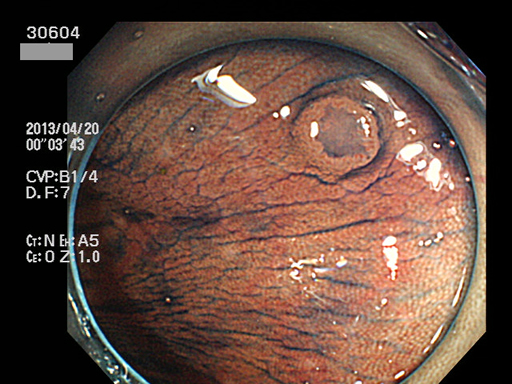

上記100名より抽出した平坦・陥凹型腺腫(=癌化の危険が高いが見落としやすい病変)の内視鏡写真

30600 30601 30603 30604 30605 30607 30609 30611 30612 30616 30619 30620